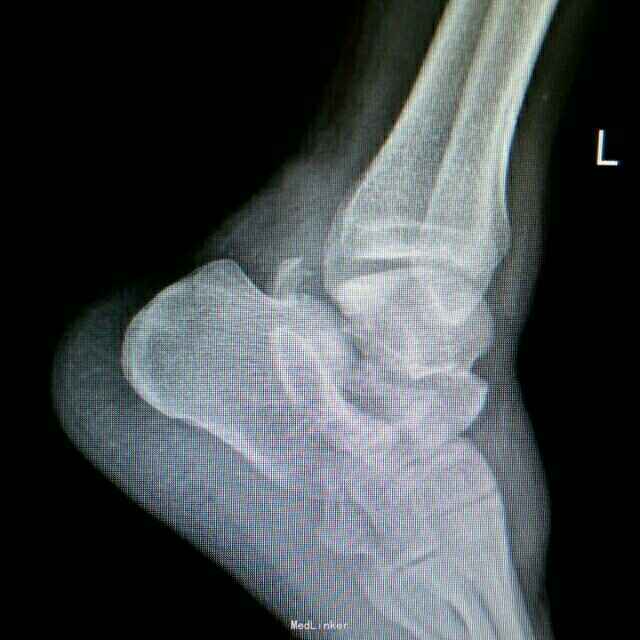

距骨骨折并脱位

重物砸伤左足疼痛畸形14小时。

左踝至中足肿胀,左足内翻畸形,皮肤可见少许细小水泡,压痛,足背动脉搏动可,足趾活动可,感麻木。

距骨骨折并脱位 入院行闭合手法复位失败,予以跟骨牵引5天,石膏外固定3天,皮肤水泡、肿胀消退后行,距骨骨折脱位切开复位内固定+距舟关节融合。术后支具外固定,勿负重3个月。